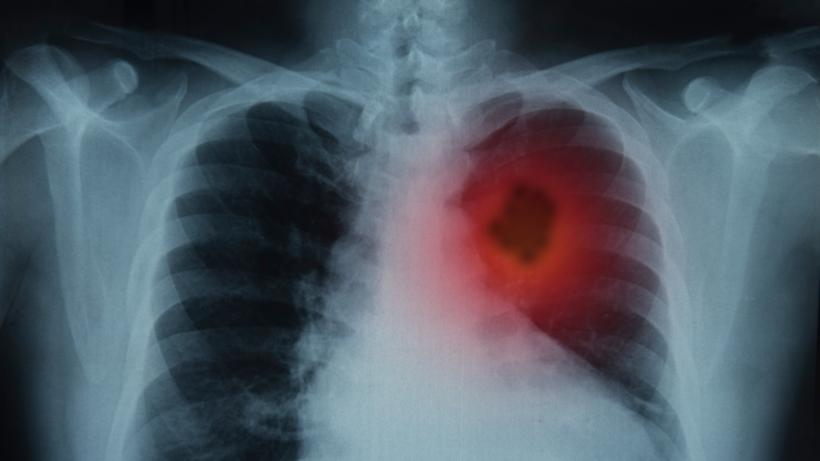

Radon: murim de la el, dar nu e grabă. Prima strategie de informare despre pericolul nevăzut din case și birouri | Galerie Foto | Imagine 3